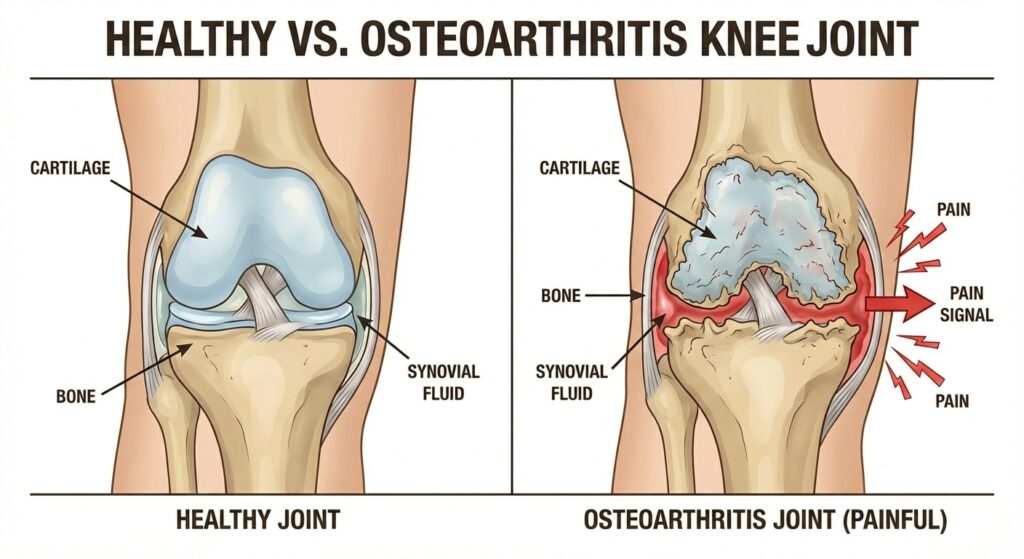

Osteoarthritis is a complex, multi-layer collapse.

Osteoarthritis happens when multiple systems break down at the same time:

❌ Cartilage slowly thinning

❌ Joint fluid losing lubrication

❌ Low-grade inflammation never fully shutting off

❌ The body’s natural repair response weakening with age

A basic turmeric pill might temporarily numb the surface swelling, but it does absolutely nothing to replace the lost synovial fluid or repair the structural bone damage underneath.

If you only treat the surface symptoms, the foundation continues to rot away beneath it.